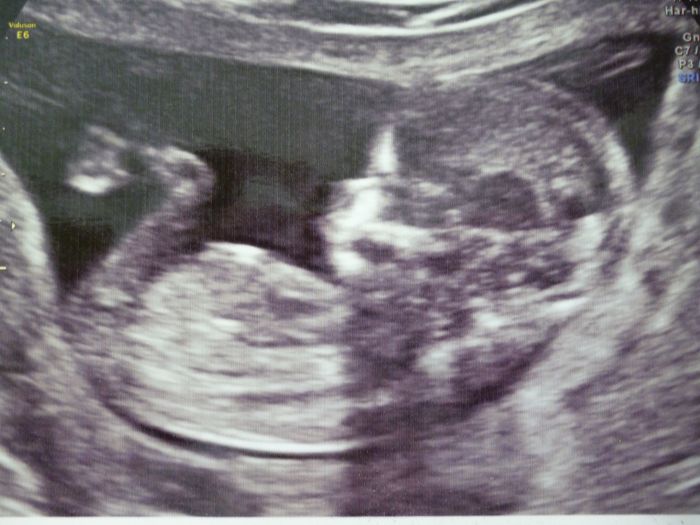

Tuli mě se zase zdá malinký,dívala jsem se na fotečka od první dcery a ta na konci 12 tt právě na genetice měla už 11 cm,ale oni ti mimísci rostou někdy rychleji,pak zase pomaleji,asi podle tabulek je to OK,když to dr říkal.....jo a musím dát fotečku z velkého UTZ,je pěkná,taková klasická jako fotka,né jen ten papírek......3d jsem nechtěla,páč si pořád skovávala obličejík rukama a i dr říkal,že by ta fotka za 200 kč nestála,tak aspon černobílá........no prostě mimi se vším všudy už,ale je fakt,že to není změřená celá délka,ale jen od kostrče prý.......s první dcerou jsem byla na genetice jinde,tak asi to dělaj jak kde.

Mirko, nádherná fotečka, to už je opravdové mimi:-)...